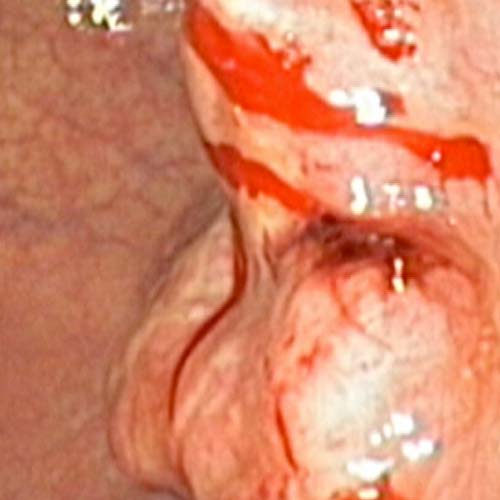

Ofrecemos procedimientos electivos y de urgencia como diagnósticos a lesiones del tubo digestivo alto y bajo, procedimientos terapéuticos endoscópicos en caso de hemorragias, obstrucción, volvulación, entre otros.

Diagnóstico precoz a lesiones del tubo digestivo alto y bajo, así como también, procedimientos terapéuticos en caso de hemorragias, obstrucción, volvulación, entre otros.